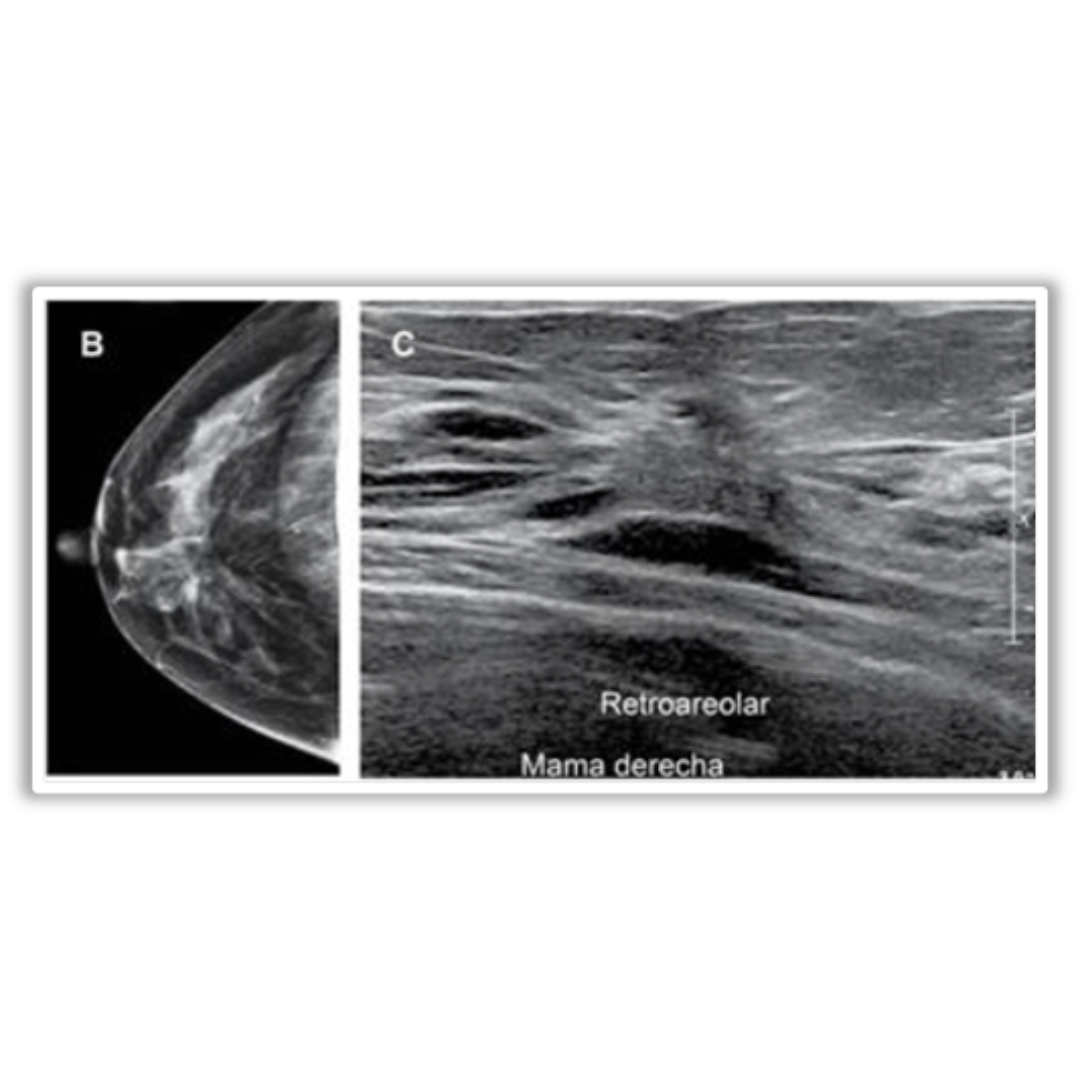

Imagen 6: B: distorsión de la arquitectura con espículas radiadas largas que confluyen centralmente. C: zona de distorsión de la arquitectura retroareolar.